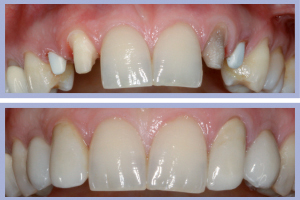

- Figg. 21a, b – Situazione clinica al momento dell’impronta per i manufatti definitivi in zirconia-ceramica

A distanza di 3 mesi dal posizionamento implantare si procedeva alla rimozione dei manufatti provvisori (monconi temporanei con relativa corona e corone provvisorie a livello degli incisivi laterali) ed alla rilevazione di una impronta degli impianti e dei monconi naturali (Figg. 21-22).

I successivi passaggi portavano all’allestimento dei manufatti definitivi in zirconia-ceramica. In particolare venivano allestite tramite procedura CAD-CAM delle cappette in zirconia da incollare sui monconi per ottenerne una individualizzazione estetica; sempre con procedura CAD-CAM si ottenevano le strutture in zirconia successivamente ceramizzate per ottenere i manufatti definitivi (Figg. 23-25).

- Figg. 27a, b – Consegna dei manufatti

- Figg. 28a, b – Confronto tra inizio e fine trattamento